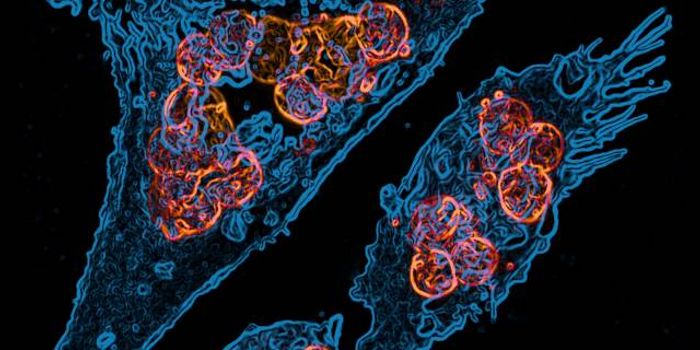

AUG 09, 2017VideosThe image described in the video above won Liang Hao a Koch Institute Image Award. She works in a lab that focuses on th ...